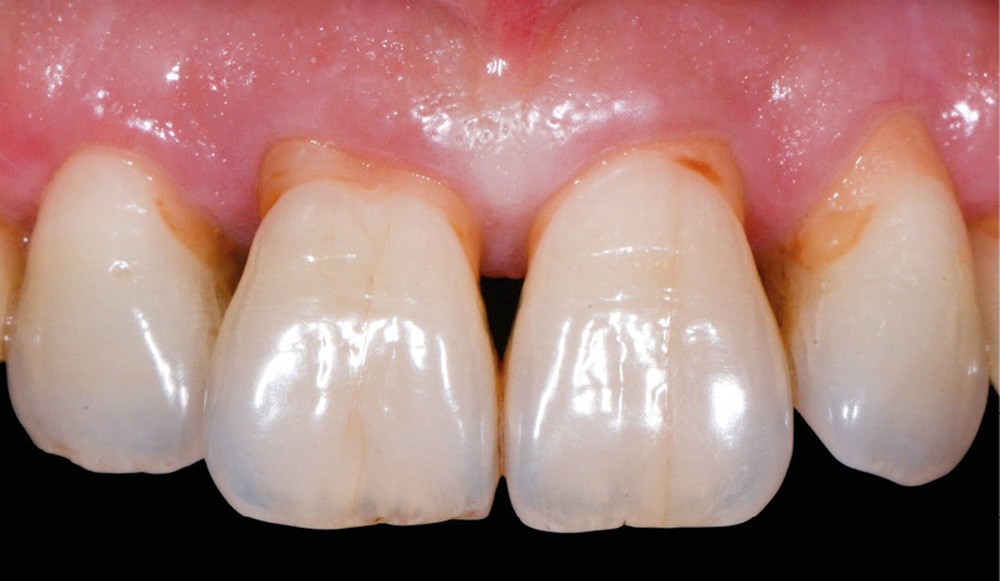

Avant tout traitement, il convient de déterminer l’étiologie des colorations dentaires. Selon leur origine, la stratégie thérapeutique et les informations délivrées au patient peuvent différer. Outre les modifications de couleur inhérentes au vieillissement des dents (fig. 1a), on distingue généralement deux types de dyschromies selon que leur étiologie est intrinsèque ou extrinsèque [2].